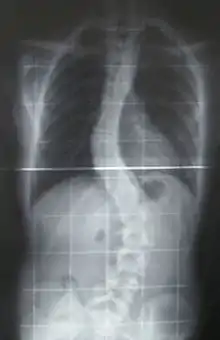

عادةً ما يسبب الجنف الالم عند البالغين وكبار السن. ويظهر في الصورة الشعاعية العمود الفقري اما على شكل حرف "S" أو حرف "C". وعادةً مايصنف على أنه عيب ولادة أثناء الولادة (بالإنجليزية: congenital)، أو مجهول السبب (بالإنجليزية: idiopathic) أو نادراً جداً على أنه مشكلة في الموصل العصبي العضلي متطورة من أمراض أخرى مثل السنسنة المشقوقة، والشلل الدماغي، ضمور العضلات الشوكي أو الصدمة البدنية.[بحاجة لمصدر] والجنف يمكن أن يصيب جميع الفقاريات وحتى الأسماك يكمن أن تصاب به. وقد عولجت أول إصابة بهذا المرض وصفت من قبل الطبيب الاغريقي ايبقراط.

يتم التشخيص بالفحص السريري والأشعة.

قياس زاوية الانحناء

طريقة قياس زاوية الانحناء من الأشعة والتي تُسمى طريقة كوب وكذلك يُطلق على الزاوية زاوية كوب. وتُقاس من الصورة الشعاعية بالطريقة التالية:

- تعيين الفقرات التي تحدد الطرف العلوي والطرف السفلي للانحناء. وهذه الفقرات هي أشد فقرات الانحناء ميلاناً تجاه الجهة المُقعرة للانحناء.

- بعد تعيين الفقرتين، يُرسم خط مستقيم يمر بالطرف العلوي للفقرة العلوية للانحناء وخط مستقيم آخر يمر بالطرف السفلي للفقرة السفلية للانحناء.

- تُحسب الزاوية التي تقع عند تقاطع هذين الخطين وهي زاوية الانحناء.

وكذلك بالأشعة يمكن معرفة ما إذا كان الجنف (الانحناء) بنيوي أو مُعاوض (تعويضي)، الانحناء المُعاوض يحدث نتيجة للانحناء البنيوي ليتوازن الجسم. تُأخذ صورة أشعة للشخص وهو منحني جانبياً لليمين وأخرى وهو منحني جانبياً لليسار، مما يؤدي إلى اختفاء الانحناء المُعاوض ولكن الانحناء البنيوي يظل. وهذه الطريقة كذلك تفيد في معرفة مرونة العمود الفقري لدى المريض.